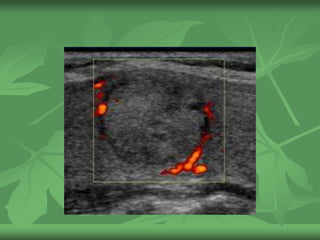

Mismo caso

Recommendation:

FNAExplanation: Color

Doppler image of the same

nodule demonstrates

predominantly internal

vascularity. Internal

vascularity is suspicious. In

this otherwise borderline

nodule, the predominant

intenal vascularity leads to

the recommendation for

FNA.

Pathology: Papillary

carcinoma